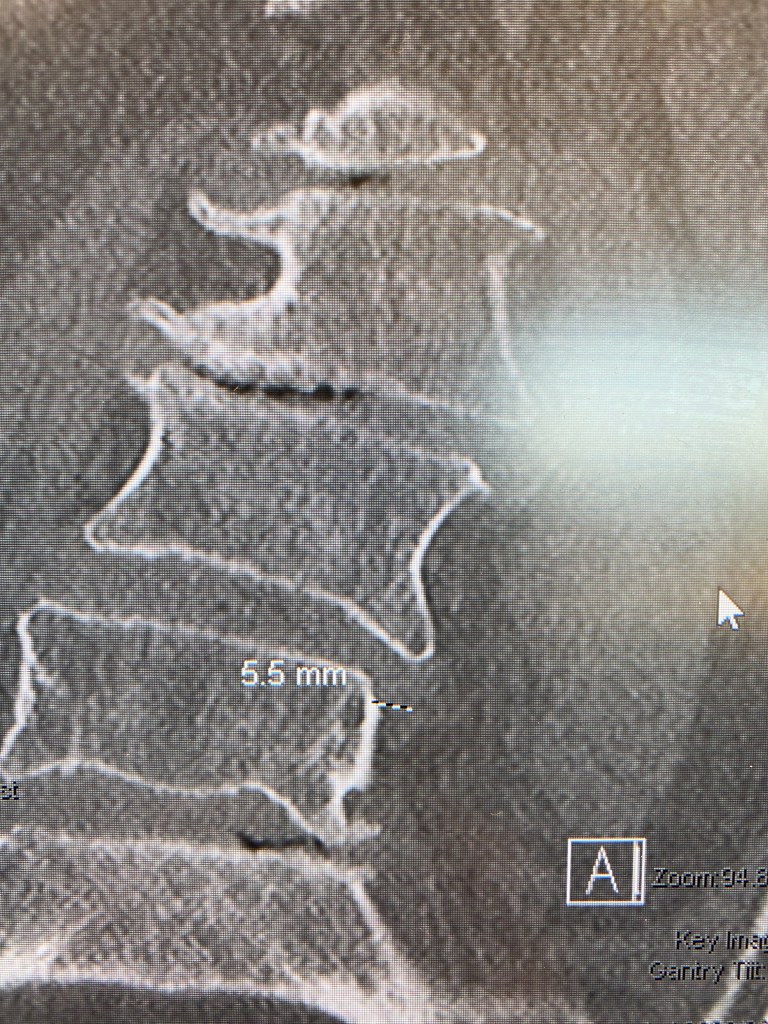

Not this part…

not even the trainwreck in the middle, just one key spot.

The x-rays are this side of obscene, but the amazing fact is that I stand straight… I just can’t keep moving for more than a few minutes.